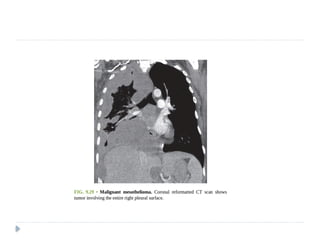

MALIGNANT MESOTHELIOMA

⚫ Highly malignant and locally aggressive tumor

⚫ 6th or 7th decade of life

⚫ Associated with asbestos exposure, with an average latency of

35-40 years for its development.

On imaging :

⚫ Diffuse nodular pleural thickening – pleura along the

intercostal spaces, costophrenic angles and lung apices

are involved.

⚫ Pleural plaques (latent period of formation is 20yrs; strong

indicator of asbestos exposure): usually seen adjacent to ribs.

Involving sixth to ninth rib. These themselves are not

premalignant

⚫ Pleural effusion

⚫ Calcifications may be seen along diaphragmatic pleura.

Malignant mesothelioma:

Axial contrast-enhanced CT scan showing enhancing

nodular pleural thickening (arrows) involving the

costal and mediastinal pleura, extending into the

major fissure (arrowhead) with crowding of ribs